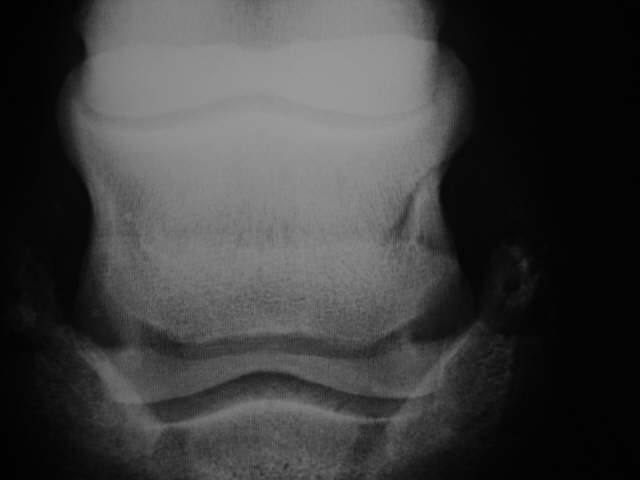

Unaufällige Gefäßkanäle

Seitlich asymetrisches Strahlbein mit leicht konkavem unterern Rand